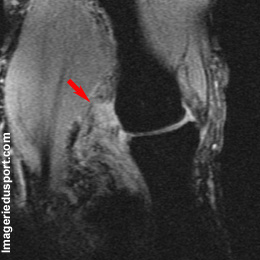

A - IRM du pouce, coupe coronale T2 : Aspect discontinu et rétracté en boule du ligament collateral ulnaire.

B - IRM, Coupe axiale T2 : Aspect rétracté en boule du ligament collateral ulnaire

Entorse du ligament collateral ulnaire avec lésion de stener associé.